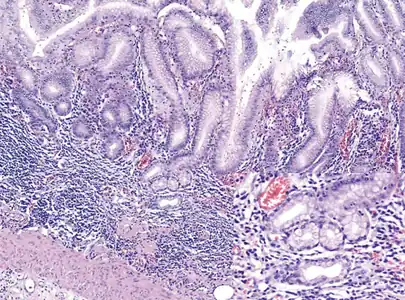

Histopathology of antral mucosa with atrophy. H&E 10x. Antral gastric mucosa with accentuated atrophy because replacement by extensive intestinal metaplasia.